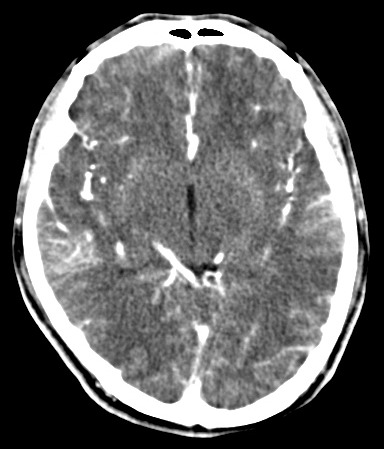

男,31岁,头疼就诊,其他不祥。

考虑右颞叶脑血管畸形伴出血。avm可能大,建议dsa。

平扫见右颞叶、右侧脑室后角旁略高密度影,增强未见明显病灶,基本正常。不放心做mri检查

病灶呈略高密度,周围伴环形水肿,无强化/无异常av影........

考虑为:1.脑内小血肿?   2.脑灰质异位?   建议mri检查........

考虑右颞叶脑血管畸形伴出血。考虑静脉血管瘤,深部型的,avm不除外,建议dsa。